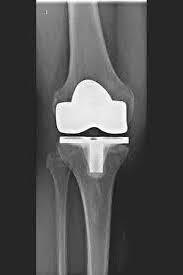

ATR (ARTICULACIÓN ARTIFICIAL DE LA RODILLA)

La articulación de rodilla artificial reemplaza la superficie del cartílago destruida por la osteoartritis. El hueso subyacente del fémur y la cabeza tibial permanece intacto. Algunos comparan una articulación artificial moderna de rodilla con la coronación de un diente; el término exacto es el llamado rejuvenecimiento bicondilar. Entre las nuevas superficies de la parte superior e inferior de la pierna se encuentra la llamada incrustación de un plástico blanco especialmente endurecido, que en la imagen de rayos X se puede ver como la distancia entre las piezas metálicas.